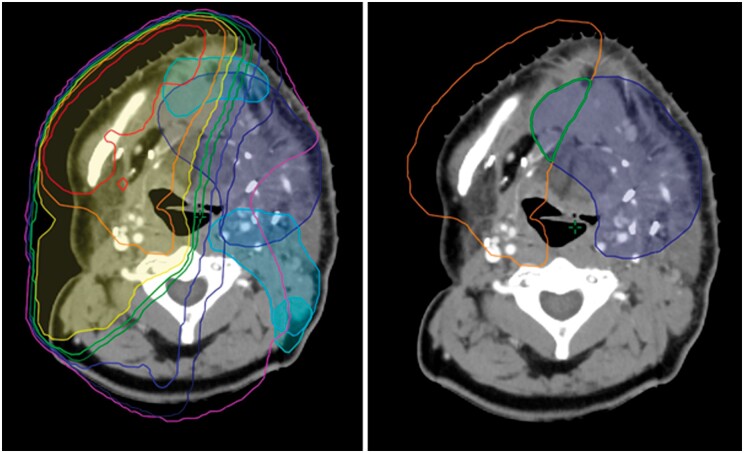

Abstract Image